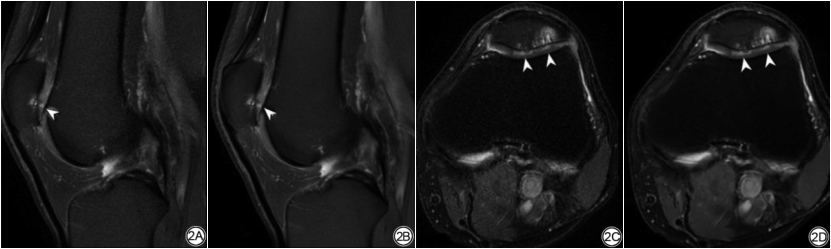

两名医师分别基于膝关节2D FSEO及FSEDL图像对膝关节结构异常进行评估,κ值在0.954~1.000之间,P<0.05。同一名医师对FSEO图像和FSEDL图像的诊断结果比较,关于软骨缺损的检测和评估,诊断结果具有较好的一致性,κ值分别为0.769、0.771,P<0.05(表5、图3);关于半月板、韧带、骨髓及滑膜液的检测和评估,诊断结果具有极好的一致性,κ值在0.944~1.000之间,P<0.05(表5、图2~3)。

在诊断效能方面,本研究表明DLR图像和原始图像对膝关节病变的显示基本一致。RECHT等[20]使用了回顾性的欠采样数据显示DL图像可与标准临床图像互换用于检测膝关节内部结构异常,DL加速图像比标准图像具有更高的图像质量。本研究对膝关节结构异常的检出和评估,DLR图像和原始图像总体无明显差异。在软骨缺损分级上,两组图像的一致性的κ值稍低(0.769和0.771),这可能因为图像通过DLR,软骨与邻近结构的对比提高,从而软骨边缘和纹理显示更清晰,因此病变显示更明显。